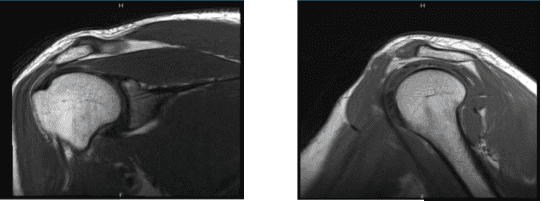

Durante los últimos meses, un paciente masculino de 36 años acudió a la consulta debido a un dolor en el hombro derecho. Realizamos una resonancia magnética que reveló enfermedad en las regiones subacromial y del labrum. La articulación AC también es sensible para el afectado. El paciente recibió tratamiento conservador, pero no se le proporcionó alivio.

Hallazgos de resonancia magnética; La evaluación de las estructuras óseas regionales no muestra evidencia de edema de médula ni deformidad de contorno que sugiera lesión ósea. Se forma un quiste subcondral, inespecífico, en la cabeza humeral superolateral poster. Las articulaciones glenohumeral y acromioclavicular suelen estar alineadas.

El proceso acromial es posterolateral inclinado hacia abajo y su superficie inferior suele ser recta en su configuración. El arco coracoacromial se acerca estrechamente al músculo/tendón supraespinoso subyacente, lo que puede manifestarse clínicamente como pinzamiento subacromial.

Hay una ruptura de las fibras insertionales inferiores del tendón infraespinoso. Los tendones supraespinoso, subescapular y tere menor no tienen nada de especial apariencia. Existe una rotura/tendinopatía parcial del tendón del bíceps intraarticular.

El segmento intertuberculoso del tendón del bíceps muestra curso y morfología normales. Hay deshilachamiento del labrum superior, así como deshilachamiento del ancla superior del tendón labrum-bíceps del tubérculo supraglenoideo. Esto es compatible con una lesión SLAP (labrum anterior-posterior superior).

El resto del labrum glenoide permanece intacto. La musculatura regional está bien desarrollada, sin evidencia de edema o atrofia. Hay una pequeña cantidad de líquido fisiológico dentro de la articulación glenohumeral.

No hay fluido dentro de las bursas subacromiales-subdeltoides o subcoracoideas. Se nota incidental sobre un lipoma subcutáneo en los tejidos blandos en la parte posterosuperior del proceso acromión. Mide aproximadamente 2,5 cm en la máxima dimensión.

MRI-3T Hombro derecho sin contraste